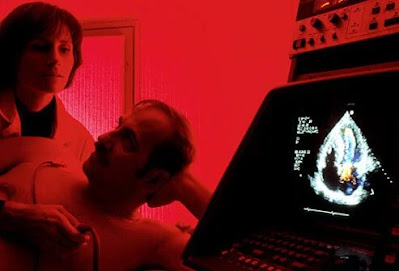

Έλεγχος καρδιακών παθήσεων: Ηχοκαρδιογράφημα

Το ηχοκαρδιογράφημα χρησιμοποιεί ηχητικά κύματα για να απεικονίσει την καρδιά.

Το ηχοκαρδιογράφημα είναι μια κινούμενη εικόνα πραγματικού χρόνου μιας λειτουργούσας καρδιάς που γίνεται με τη χρήση ηχητικών κυμάτων (υπερήχων) για τη δημιουργία εικόνων.

Τα ηχοκαρδιογραφήματα χρησιμοποιούν την ίδια μη επεμβατική τεχνολογία που χρησιμοποιείται για την εξέταση του εμβρύου κατά τη διάρκεια της εγκυμοσύνης. Μπορεί να δείξει πόσο καλά λειτουργούν οι καρδιακοί θάλαμοι και οι βαλβίδες της καρδιάς (για παράδειγμα, αποτελεσματική ή κακή δράση άντλησης, ροή αίματος μέσω των βαλβίδων), πριν και μετά τη θεραπεία, καθώς και άλλα χαρακτηριστικά.